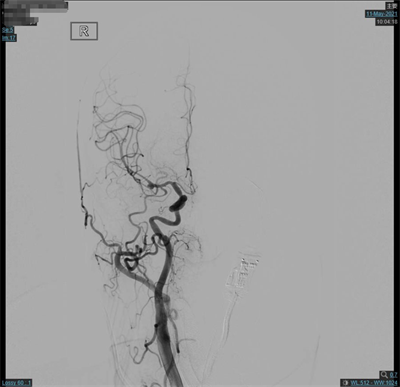

脑动脉造影(外院,2021-5-10):双侧大脑中动脉分叉多发动脉瘤。

夹闭前造影

夹闭后造影